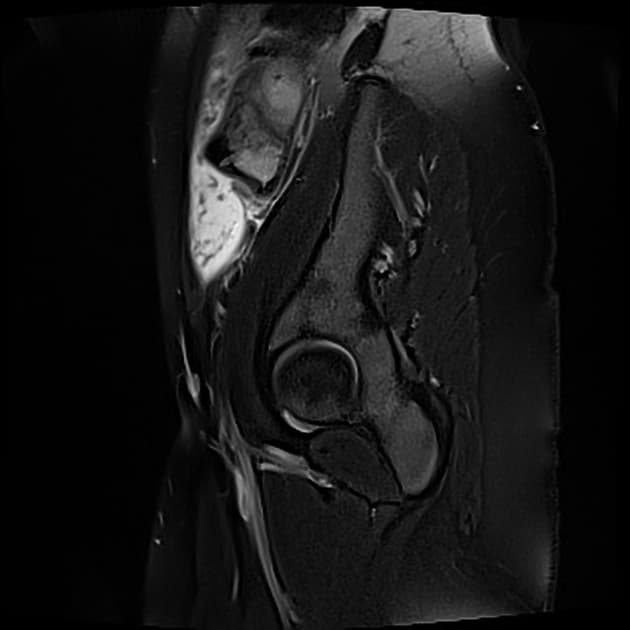

- Hình ảnh CT cho thấy các quai ruột non giãn và các mức khí-dịch, phù hợp với tắc ruột non (small bowel obstruction).

- Vị trí chuyển tiếp tại hồi tràng cuối (terminal ileum) do dày thành vòng quanh và manh tràng có vẻ teo nhỏ.

- Một số hạch bạch huyết mạc treo (mesenteric lymph nodes) phì đại được thấy ở hố chậu phải.

- Vùng hồi manh tràng là vị trí thường gặp nhất của lao trong đường tiêu hóa. Tuy nhiên, hình ảnh học không đặc hiệu cho lao. Chẩn đoán phân biệt bao gồm bệnh Crohn và ung thư manh tràng (carcinoma of the cecum). Chẩn đoán lao đã được xác nhận bằng giải phẫu bệnh (histopathology).

Lao hồi manh tràng là vị trí phổ biến nhất của lao đường tiêu hóa, đặc biệt thường gặp ở vùng lưu hành và người suy giảm miễn dịch. Nhiễm trùng mạn tính do Mycobacterium tuberculosis gây viêm xuyên thành, dẫn đến dày thành ruột, hẹp lòng và biến đổi xơ. Hồi tràng cuối và manh tràng dễ bị tổn thương do chứa nhiều mô lympho và tình trạng ứ trệ nhu mô ruột. Các dấu hiệu hình ảnh điển hình gồm dày thành không đối xứng hoặc đối xứng, manh tràng teo nhỏ và hạch mạc treo phì đại hoại tử. Mặc dù hình ảnh gợi ý, nhưng không đặc hiệu và dễ nhầm với bệnh Crohn hay ung thư manh tràng. Do đó, cần bằng chứng vi sinh hoặc giải phẫu bệnh như u hạt hoại tử bã đậu hoặc trực khuẩn kháng cồn-xiêm dương tính để chẩn đoán xác định. Nhận biết sớm và điều trị kịp thời giúp ngăn ngừa biến chứng như thủng, rò và hẹp ruột.